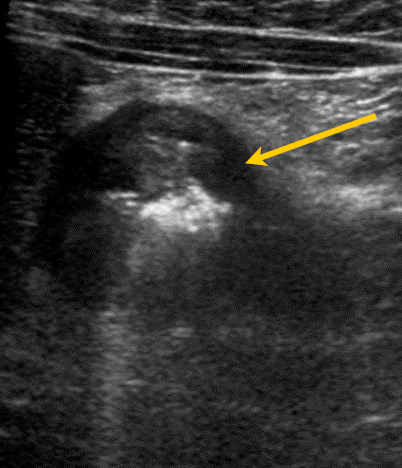

Se solicitó una ecografía abdominal, donde se objetivó un engrosamiento marcado de la pared duodenal y cambios inflamatorios yuxtaduodenales (Figs. 1 y 2). Además, se realizó analítica sanguínea y de orina, sin alteraciones; estudio microbiológico fecal negativo.

| Figura 2. Sección transversal del duodeno. Con la flecha amarilla remarcamos el importante engrosamiento de su pared. La pared del duodeno se ve de color oscuro. Los tonos blancos de su interior corresponden al contenido intestinal |